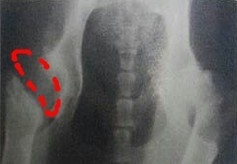

先天的髋关节发育不良犬即使年轻期没有表现症状,到老年期会更早出现严重的退行性病变,此类犬的关节一般为亚脱位状态。严重的亚脱位牵引纤维关节囊,在犬10月龄左右就会引起疼痛和跛行。由于动物每走一步,股骨头从髋臼内像活塞一样运动出来,长期如此活动,磨损,使得髋关节翘起、太高,也使得关节接触面承受的压力增大,关节面磨损。且会发生髋臼骨小梁骨折,动物出现疼痛和跛行。